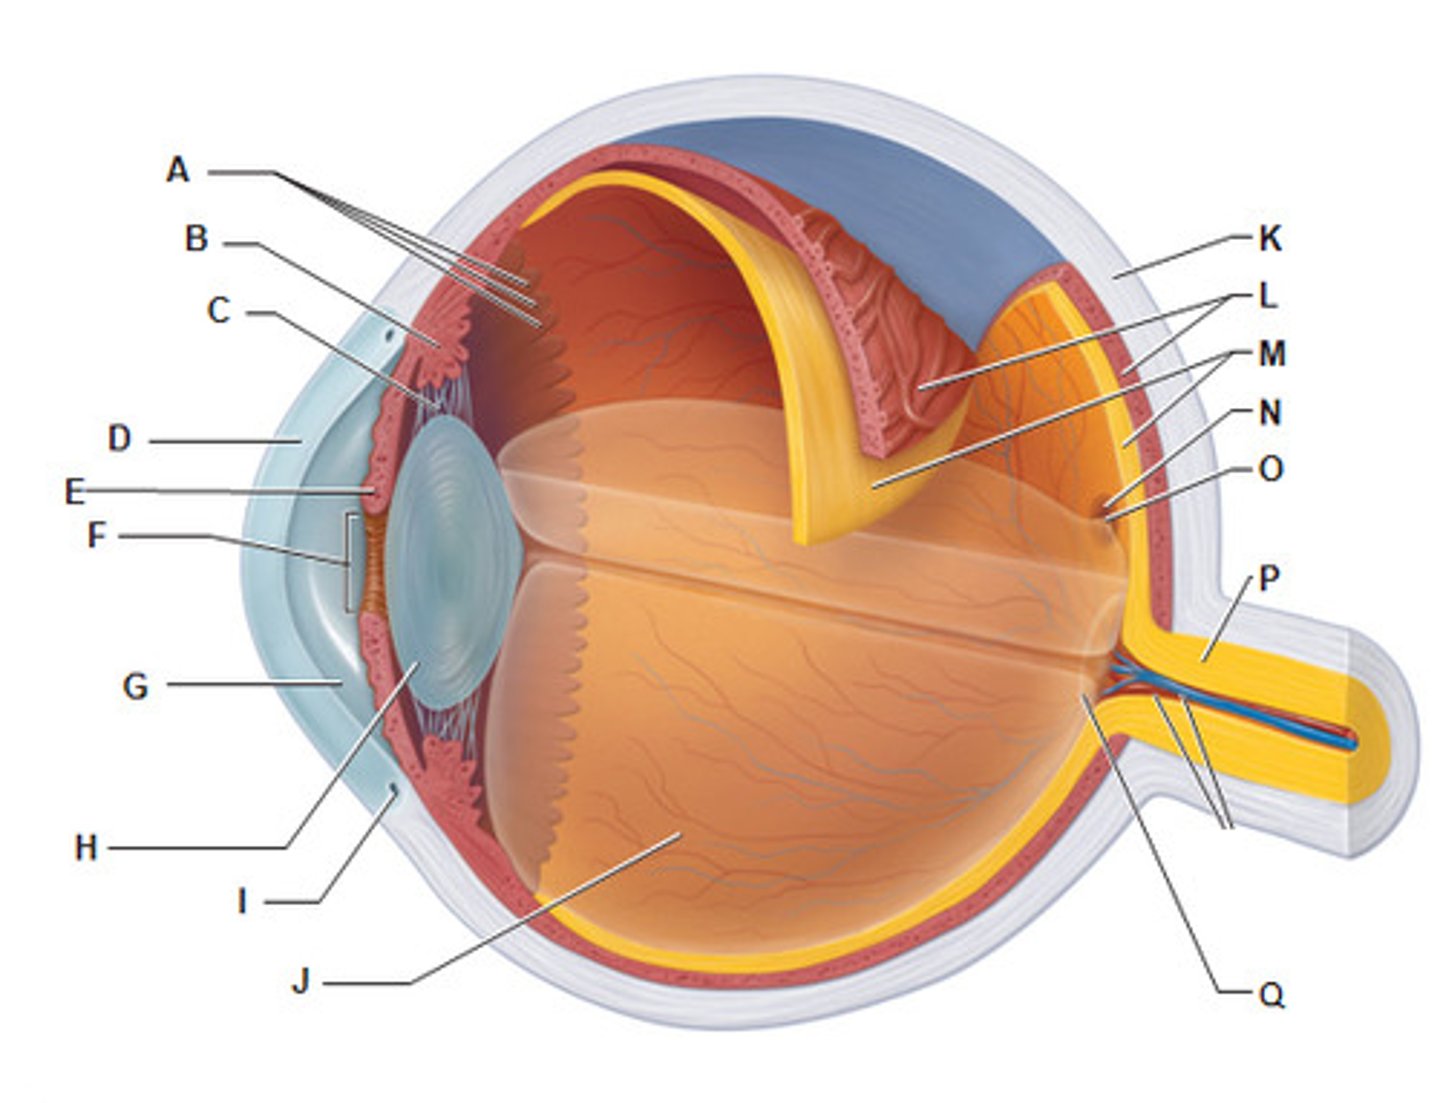

anterior cavity (of eye)

iris

B

optic disk (blind spot)

choroid

L

ciliary body

B

ciliary process

conjunctiva

cornea

D

fovea centralis

suspensory ligaments

C

vitreous humor

lens

H

macula lutea

nasolacrimal duct

lacrimal gland

posterior cavity (of eye)

pupil

F

retina

M

sclera

optic nerve